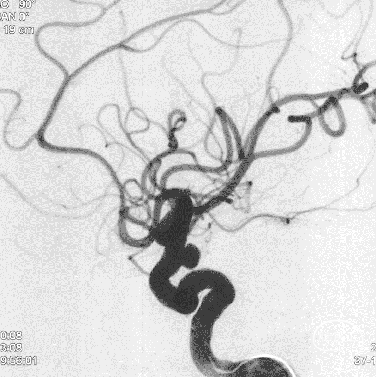

选择工作角度

压颈试验:前交通开放

Fastrack微导管到位